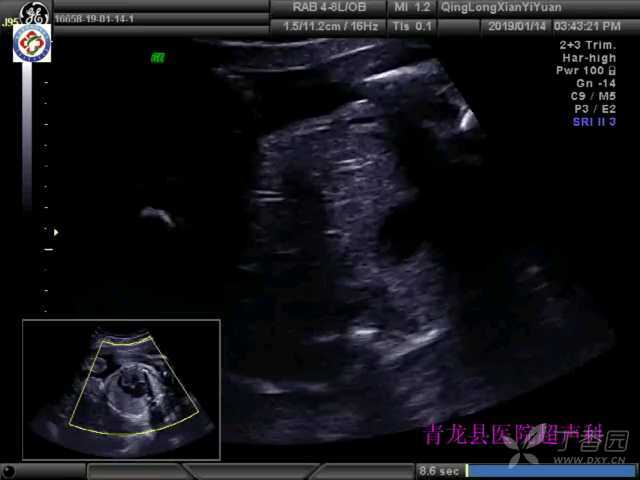

胎儿三尖瓣闭锁一例

32岁孕妇,于孕26周超声检查发现胎儿心脏异常。

6.超声表现:四腔心切面右心房室间无正常瓣膜结构,无瓣膜开放及关闭活动,无彩色多普勒血流信号通过,上、下腔静脉血液进入右心房后全部通过卵圆孔进入左心房,左心房室增大,二尖瓣反流,室间隔缺损,左心室血液通过室间隔缺损处流入右心室,室间隔缺损小或无右心室明显缩小。主动脉内径增宽,肺动脉内径变窄,肺动脉瓣口血流呈混叠色彩。三尖瓣闭锁与单心室鉴别困难。